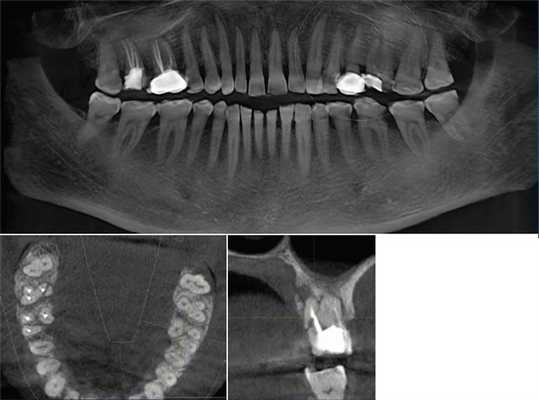

Сверхкомплектный зуб определен как парамоляр. Коронка парамоляра имела два бугорка и весьма сильно напоминала строение постоянного премоляра. Зуб повернут по оси, с расположением щечной поверхности дистально и мезиальной поверхности щечно. На мезиальной стороне парамоляра обнаружено кариозное поражение (Фото 2). Осмотр мягких тканей выявил воспаление пародонта между первым и вторым молярами и парамоляром. Сделаны рентгеновские снимки: панорамный, прицельный и окклюзионный. Чтение панорамного снимка было затруднено из-за небного расположения зуба. На прицельном и окклюзионных снимках обнаружено, что сверхкомплектный зуб поражен кариесом и имеет один корень (Фото 3 и 4).

Фото 3: Прицельный рентгеновский снимок, показывающий парамоляр с полностью сформованным зубом (указан стрелкой).

Фото 4: Окклюзионная рентгенограмма верхней челюсти, показывающая сверхкомплектный зуб (стрелка).

Наиболее ценным рентгенографическим исследованием является ОПГ с дополнительными прицельными снимками и снимками верхней и нижней челюсти в окклюзионной плоскости. Для четкой локализации непрорезавшегося зуба используют технику вертикального или горизонтального параллакса. Параллакс - это изменение обзора объекта на определенном фоне, основанное на перемещении обозревателя. Данная техника может быть осуществлена путем изготовления снимков одной зоны, но с разных углов двумя разными аппаратами. При использовании этого метода, как правило, точкой отсчета является корень примыкающего зуба. Вдобавок возможно использование конусно-лучевого КТ. Эта технология дает трехмерное изображение структур указанной зоны и является невероятно информативной при описываемой аномалии.